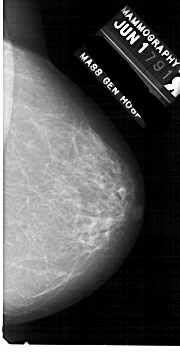

A_1870_1.RIGHT_CC

RIGHT_CC LINES 5266 PIXELS_PER_LINE 2686 BITS_PER_PIXEL 12 RESOLUTION 43.5 NON_OVERLAY